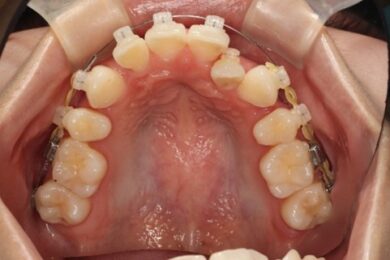

上顎のビフォアアフター

抜歯して空いたスペースが少しずつ埋まってきているのが分かりますね。

2か月前 現在

上顎の方は左の前から2番目の歯が入るスペースを確保するために、3番目の犬歯を奥の方(後ろ)に下げていきます。

右側も同様、全体を奥の方(後ろ)に下げていきます。

左の2番目の歯が前方に出てくるためにはスペース確保が必要です。歯と歯の間を広げてスペースができたらやっとブラケットが付けられます。